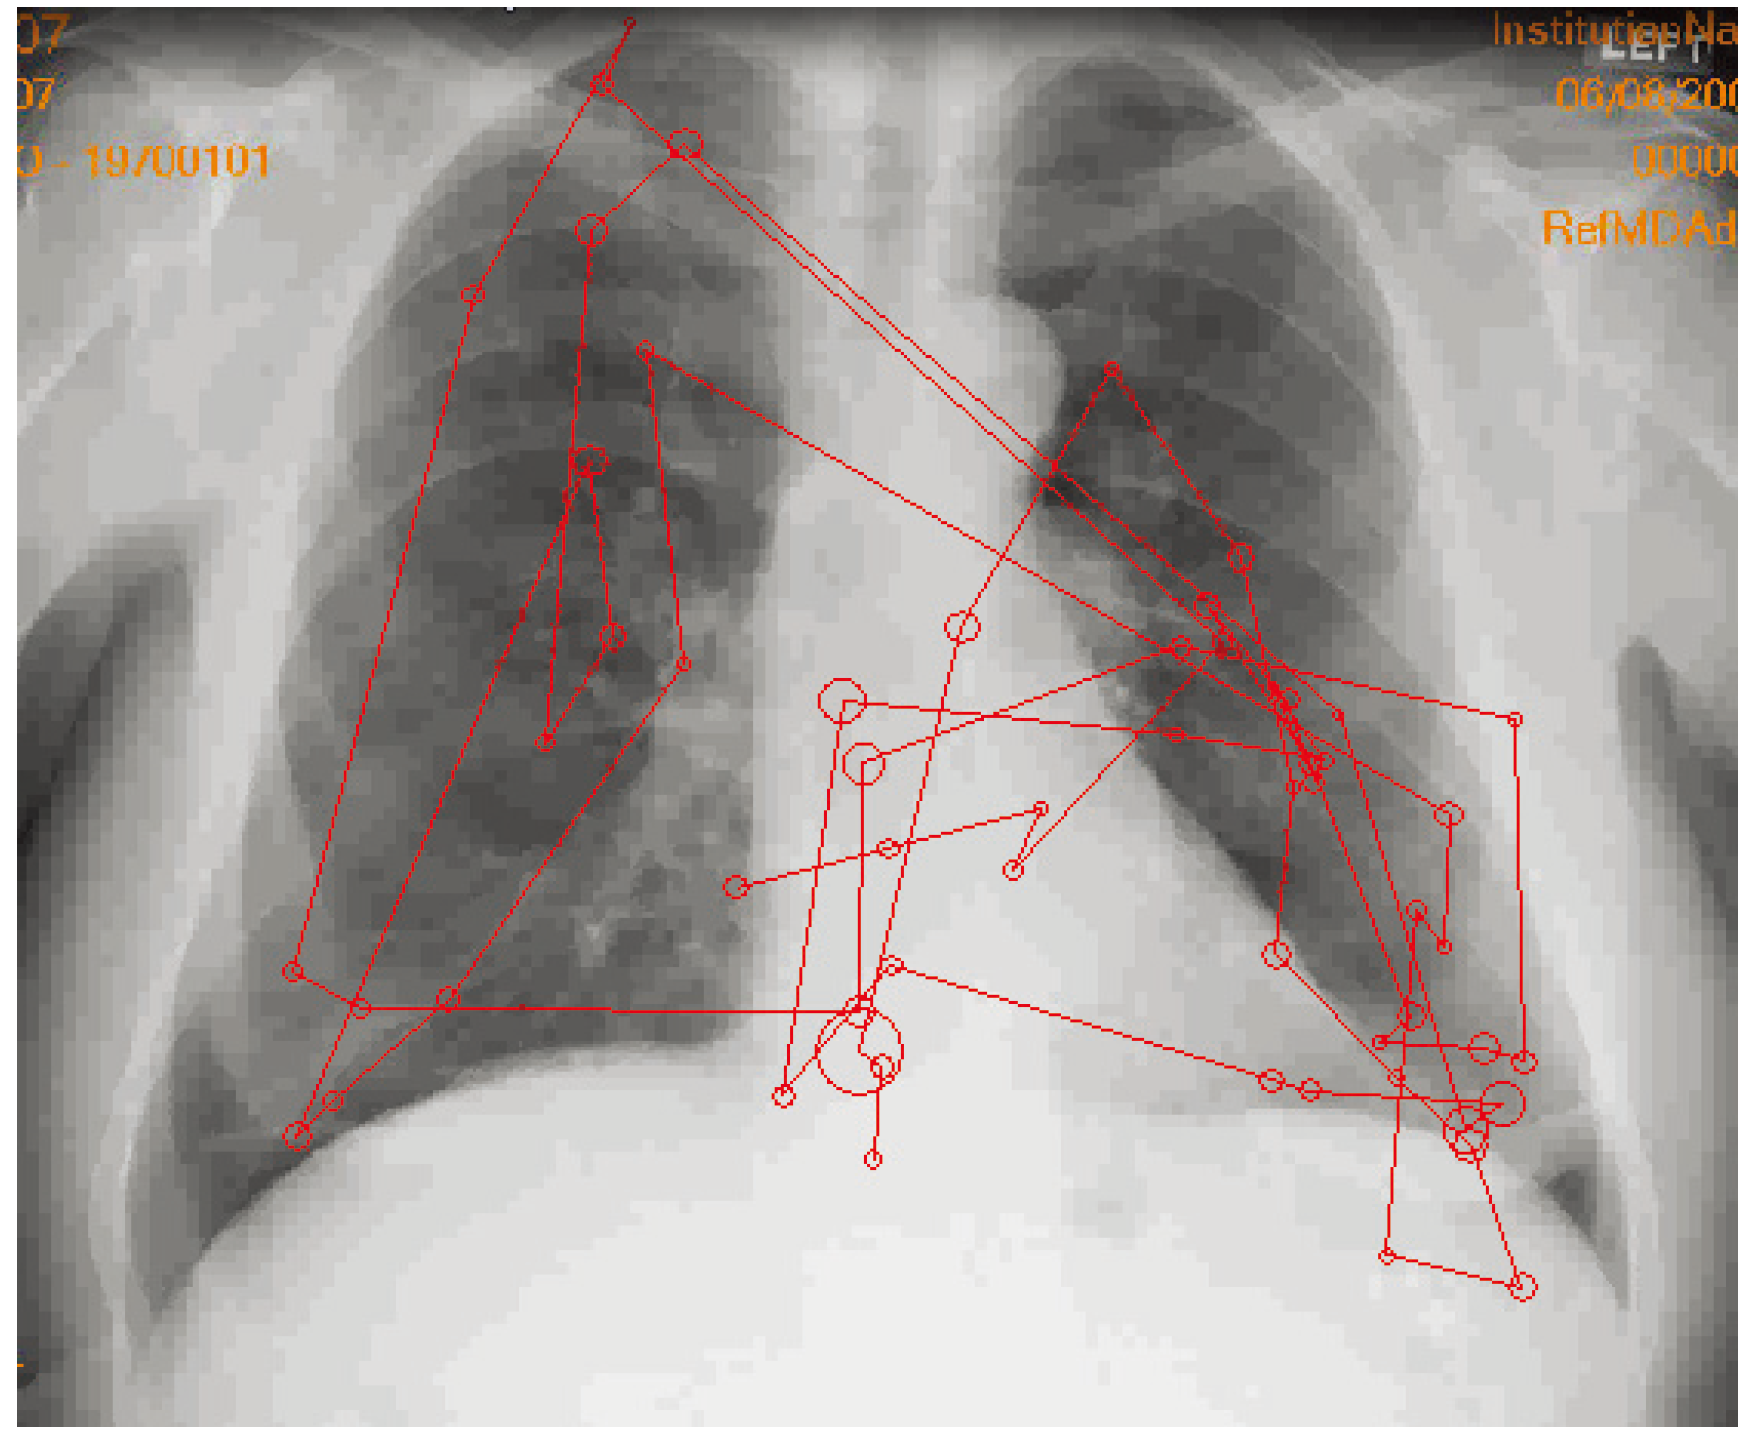

- Kundel, H.L.; Nodine, C.F.; Carmody, D.P. Visual scanning, pattern recognition and decision-making in pulmonary tumor detection. Invest. Radiol. 1978, 13, 175–181. [Google Scholar] [CrossRef]

- Kundel, H.L.; Nodine, C.F.; Krupinski, E.A. Searching for lung nodules: Visual dwell indicates locations of false-positive and false-negative decisions. Invest. Radiol. 1989, 24, 472–478. [Google Scholar] [CrossRef]